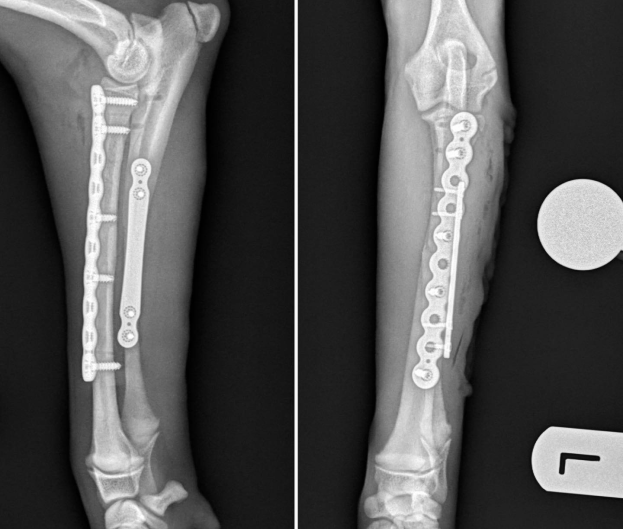

Con objeto de alcanzar un diagnóstico definitivo, realizamos un estudio radiológico de la región afectada incluyendo las proyecciones mediolateral y craneocaudal. En las imágenes obtenidas se observó una fractura oblicua corta diafisaria proximal de radio y cúbito con desplazamiento de los fragmentos óseos.

Planteamos la reducción y estabilización de las fracturas descritas mediante sendas placas de bloqueo fabricadas en titanio tipo PAX, una de reconstrucción de 2,7 mm en el radio y otra de elongación de 1,5 mm en el cúbito.

El procedimiento quirúrgico se llevó a cabo realizando un abordaje craneolateral al radio y cúbito. En primer lugar se reduce y estabiliza la fractura del radio y posteriormente el cúbito. La estabilización se consigue gracias a las placas de osteosíntesis descritas. En el radio se aplican dos tornillos en el fragmento proximal y tres en el distal. En el cúbito se emplean dos tornillos por fragmento.

Realizamos unas radiografías de control postquirúrgicas, en las que comprobamos que la reducción anatómica de las fracturas y que la colocación de los implantes es la deseada respetando las líneas de crecimiento.